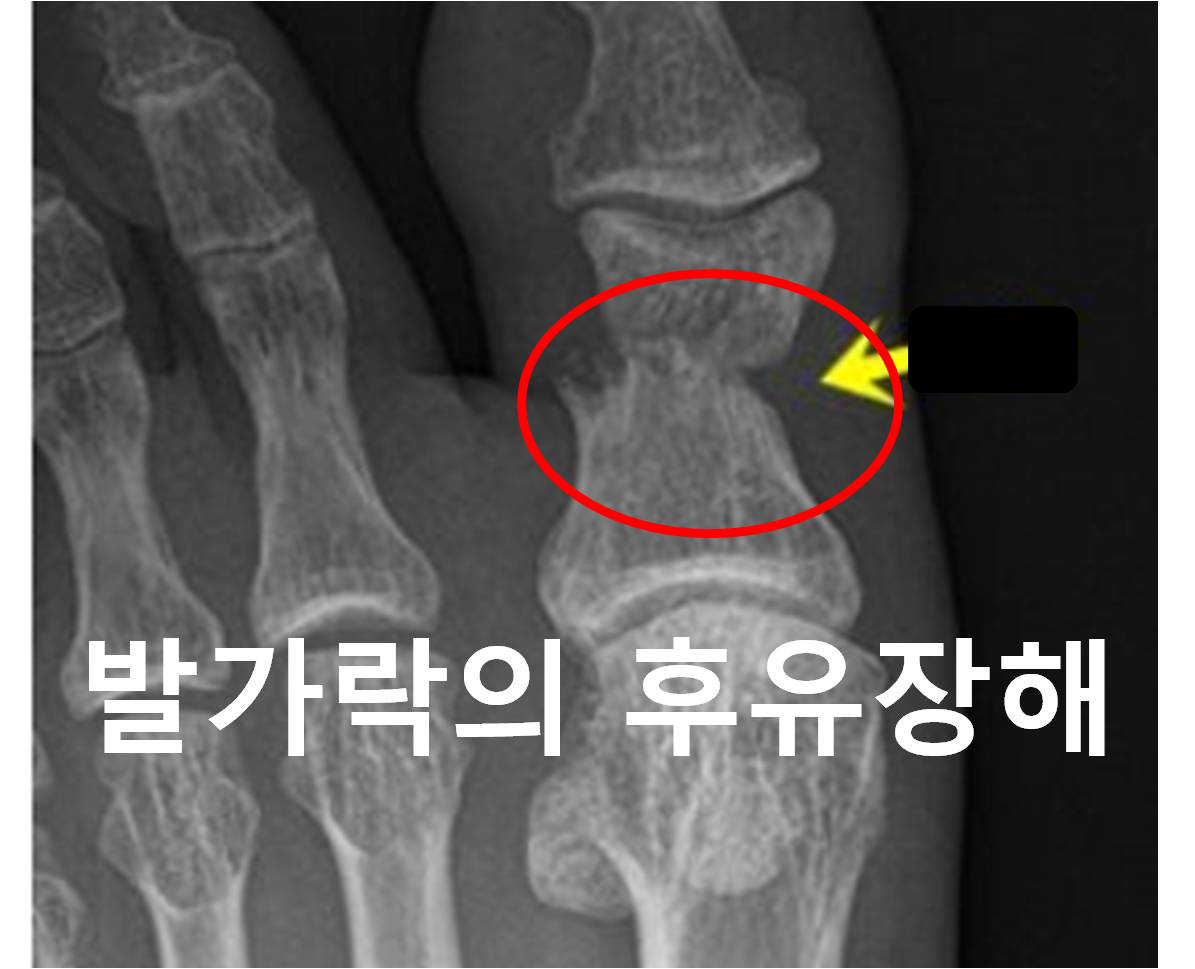

• 발가락의 후유장해 보험금 손해사정 사례

안녕하세요. 더애플손해사정입니다.^^오늘은 발가락의 후유장해에 대해서 알려드리겠습니다. 발가락은 우리몸의 가장 끝에 위치해서 그 기능을 크게 인정받기 못해서 소외받는 신체부위 중 하나이기도 합...